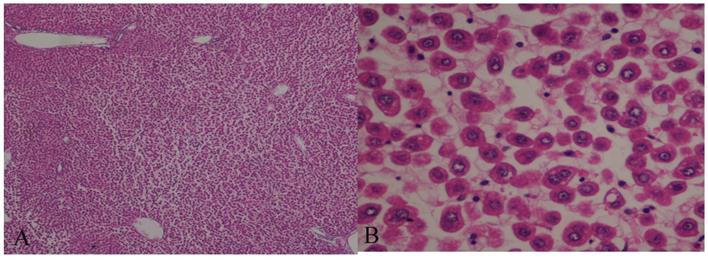

The histological evaluation of the hepatic tissue from the control group showed normal liver architecture. In Group A, the hepatic tissue was preserved, and there was no evidence of an inflammatory infiltrate, steatosis, or fibrosis. The structural integrity of the nuclei and organelles within the hepatocytes was maintained, and there was no evidence of necrosis or apoptosis. In Group B, the structure of the hepatic parenchyma was preserved, but the hepatocytes showed moderate-to-severe disassociation and some ballonization. The structural integrity of the organelles and nuclei within the hepatocytes was maintained, and neither apoptosis nor necrosis was visible (Figs. 7 and 8).

Figure 7

Hematoxylin and eosin (H&E)-stained sections of hepatic tissue from the hypothermic reperfusion group. The hepatic sinusoids do not show endothelial injury, and the hepatocytes contained normal intracellular organelles and nuclei, with no signs of apoptotic or necrosis (A: H&E 40×; B: H&E 400×).

Figure 8

Hematoxylin and eosin (H&E)-stained sections of hepatic tissue from the normothermic reperfusion group. The hepatic parenchyma architecture is preserved without lesions. There is moderate-to-severe disassociation of the hepatocytes. The hepatocytes contain normal nuclei and organelles, with no signs of necrosis or apoptosis (A: H&E 40×; B: H&E 400×).